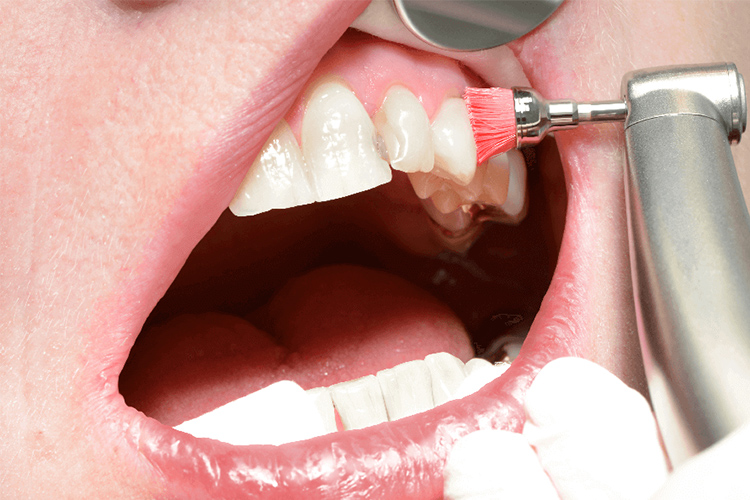

PMTC(プロフェッショナル・メカニカル・ティース・クリーニング)

普段の歯磨きでは難しい歯と歯の隙間や、口腔内の隅々を専用の機器を使用してケアします。歯磨きだけでは落としきれない汚れや歯垢の元になるバイオフィルムも除去します。

PMTCは歯周病改善だけでなく虫歯も防ぎ、歯質強化、着色除去して光沢感を出す効果もあります。